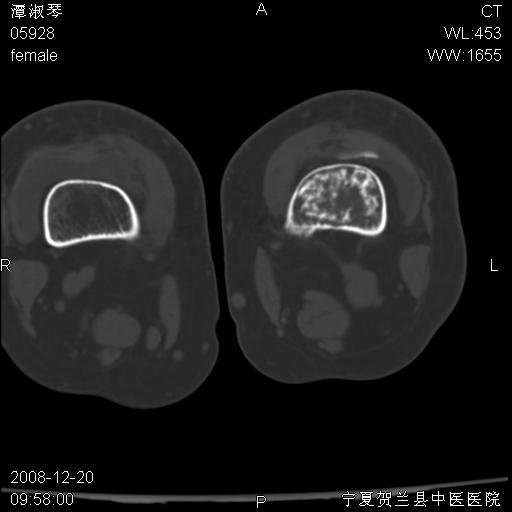

标题: CT17526:请各位看看是啥? [打印本页]

标题: CT17526:请各位看看是啥?

内生软骨瘤?骨梗死?

考虑内生软骨瘤可能性大

考虑-----骨梗死+退变

支持骨梗死,退行性骨关节病,膝关节积液.

考虑骨梗死可能性大

支持骨纤或内生软骨瘤或骨梗死,退行性骨关节病,膝关节积液.

骨梗死可能性大

左股骨下段骨梗死。双膝退变。

支持:内生软骨瘤或骨梗死!另:退行性骨关节病,膝关节积液。

左胫骨下端松质骨及髓腔内可见点片状高密度灶,骨皮质无明显膨胀及变薄。病变范围较长。支持骨梗死,退行性骨关节病,膝关节积液